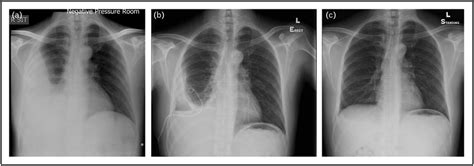

Tuberculous Pleuritis: Radiological Characteristics and Diagnostic Yield Correlation